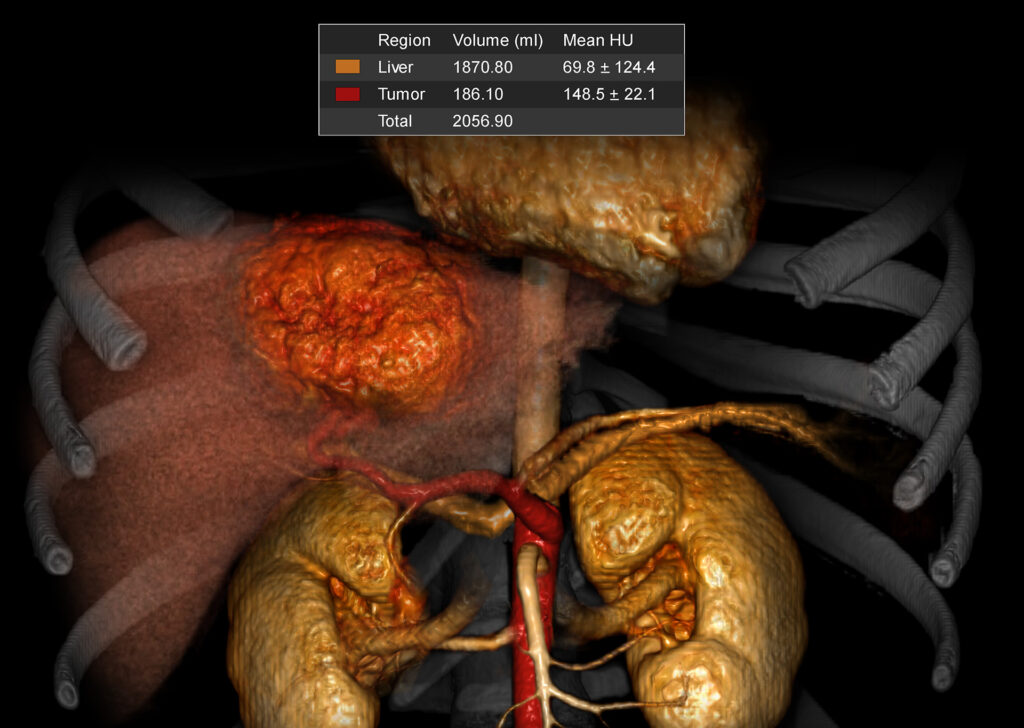

CT Liver Analysis and Resection Planning

CT Liver Analysis provides tools for segmenting and quantifying the liver and liver-related tumors. It provides automatic registration for display of multiple series, optimized screen layouts and quantification tools for routine clinical measurements.